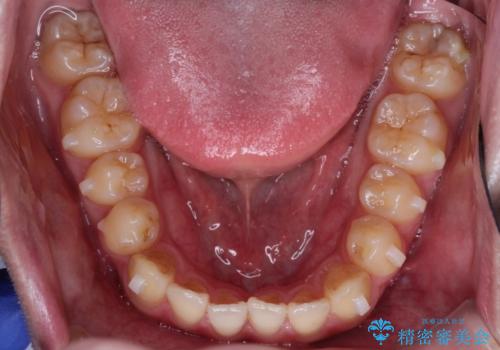

前歯のデコボコ インビザラインによる目立たない矯正

- 前歯のデコボコを主訴に来院された患者様です。

目立たないそうちをご希望されたので、インビザラインにて治療することとしました。

歯と歯の間をわずかに削ってスペースをつくり、デコボコを改善しました。